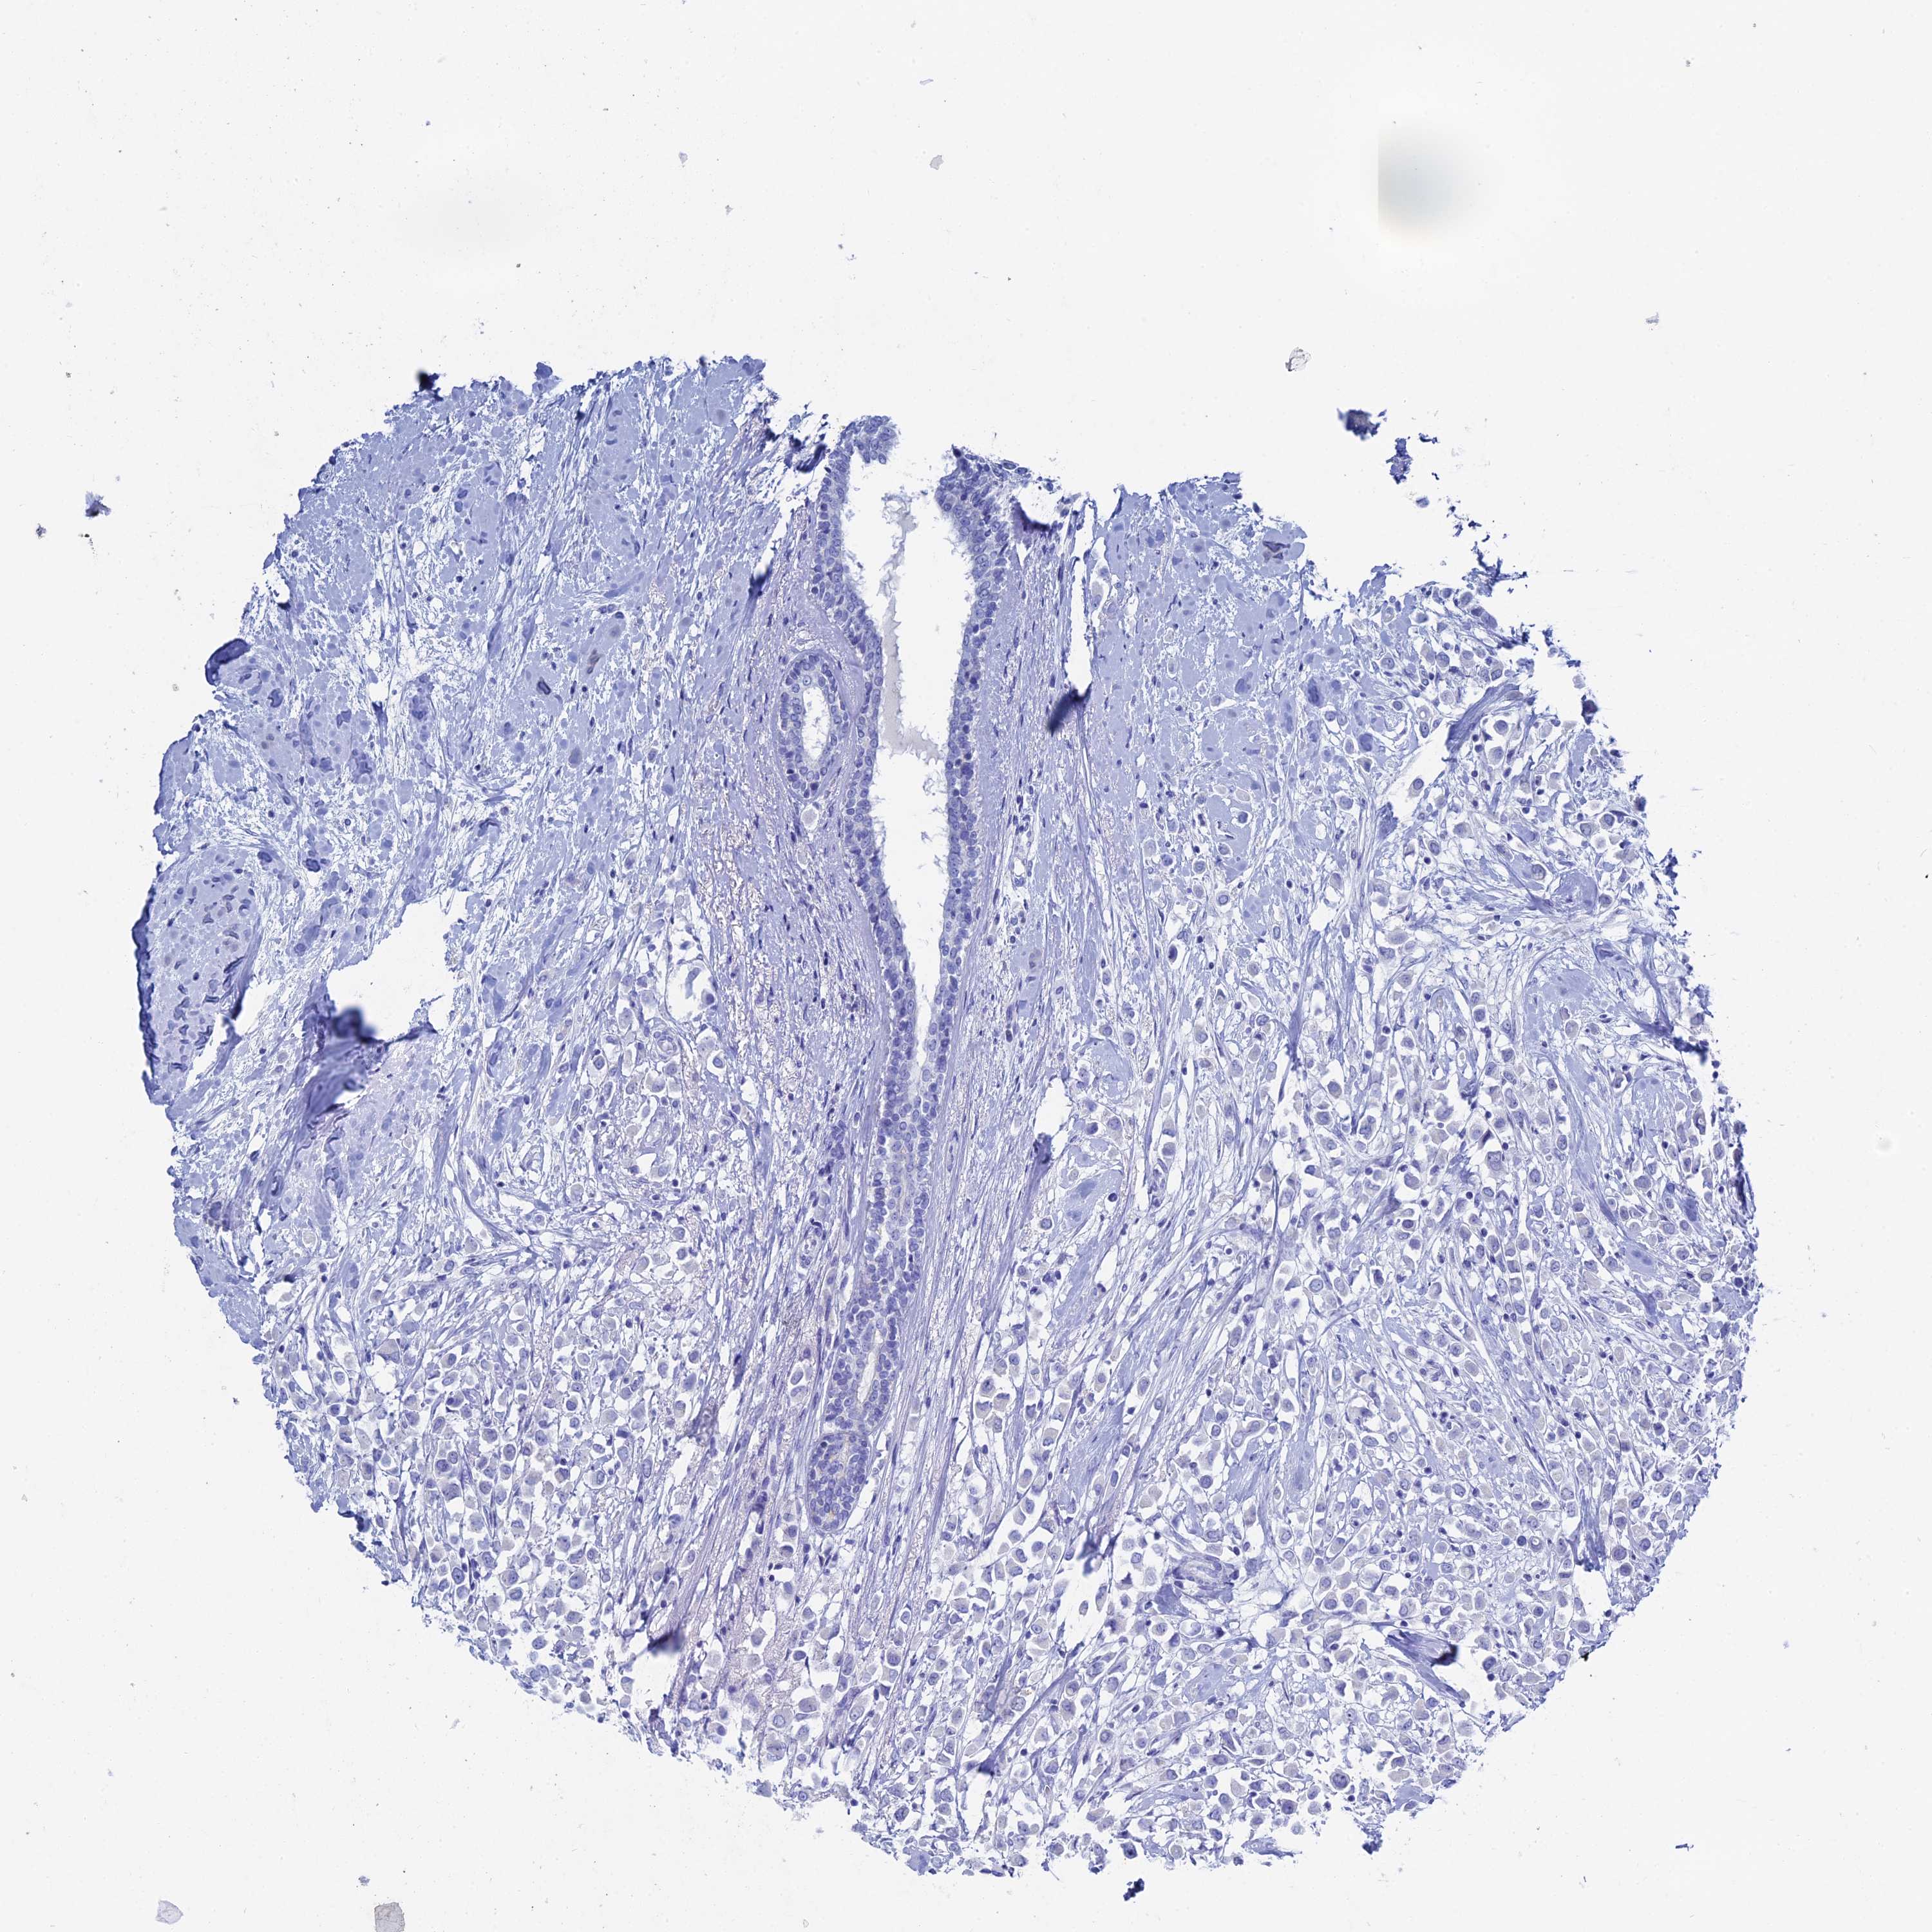

Breast cancer

Human cancer